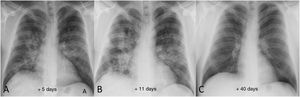

Radiological examples of long-term post-COVID-19 progressionA significant percentage of patients with SARS-CoV-2 pneumonia have radiological abnormalities on the follow-up chest X-ray one month after hospital discharge. In these patients we generally recommend/perform a chest CT without intravenous contrast. In our experience, the severity of the clinical picture usually implies a greater radiological involvement of the lung parenchyma after hospital discharge and a slow favourable response on imaging tests (Fig. 7), especially in patients who required prolonged ICU stays. We do not yet know how much time is needed to establish that the residual radiological findings are stable and definitive. However, some patients with mild or moderate pneumonia may achieve complete resolution of the radiological findings in the first months after discharge (Fig. 8). Ground-glass opacities are among the imaging abnormalities that tend to resolve earlier, while subpleural bands, bronchial dilation and subpleural interstitial involvement usually follow a favourable course that progresses slowly (Figs. 9 and 10). There is, therefore, great variability among patients in the time it takes for residual post-COVID-19 radiological findings to resolve or stabilise. The severity of the clinical picture is probably the most determining factor.

Example of good radiological recovery on chest X-ray in a 39-year-old male patient. A) Five days after the onset of symptoms, bilateral opacities can be seen, predominantly perihilar. B) 11 days after the onset of symptoms, radiological worsening is identified (greater density and extension of the opacities). C) Once discharged from hospital, follow-up chest X-ray 40 days after onset of symptoms shows complete radiographic resolution of the lung opacities.